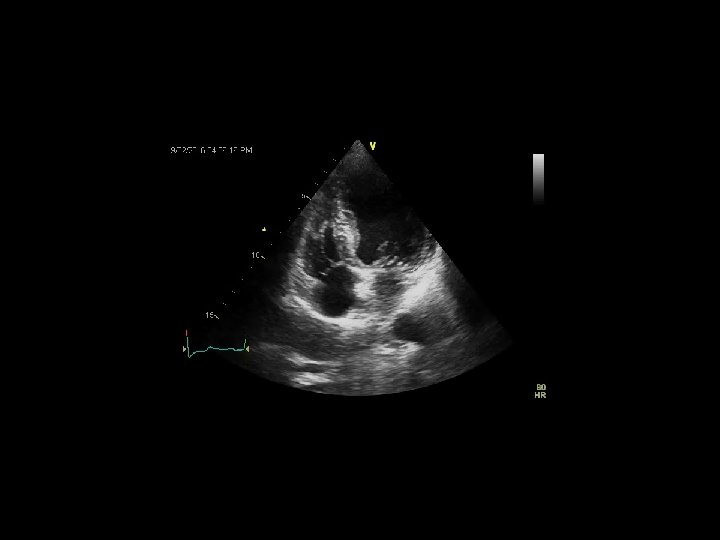

AORTIC STENOSIS Echocardiography 1. Anatomy - short & long axis views (occasionally TEE / 3 D) 2. LVOT diameter – midsystole ; at the site of measurement of LVOT velocity measurement parallel to AV 3. LVOT velocity - apical 4 C / 5 C ; V max / VTI 4. AS jet velocity (CW) – V max; peak and mean gr; VTI 5. SVI 6. DSE ( SOS)